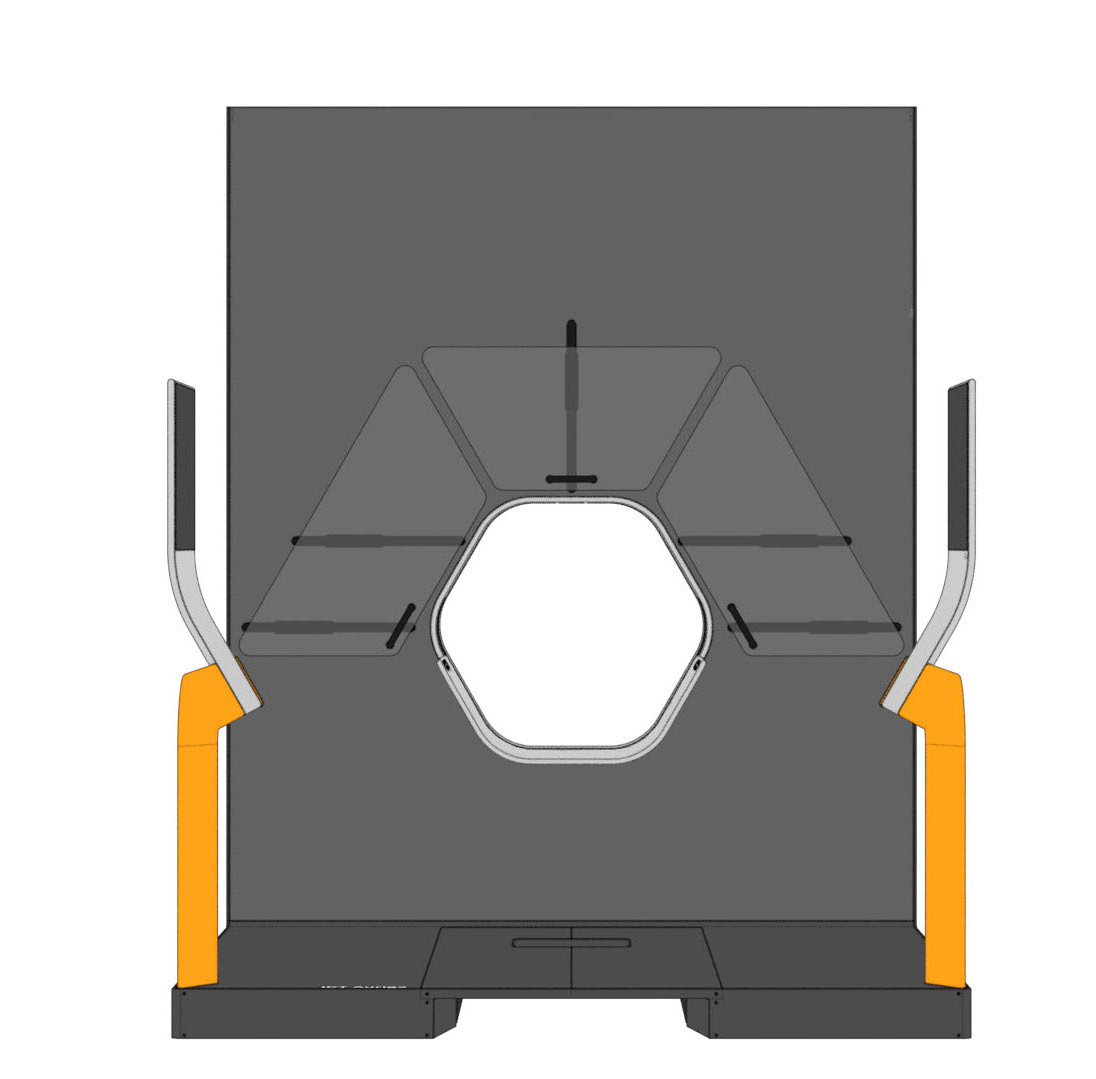

Auriga is an architecturally inspired CT device. The gantry extends to the ceiling and becomes a spatial installation. This takes away its massive “machine-character” and makes it part of the room. The gantry height is individually adapted to the given space - individuality becomes part of the product. In order to enable right- and left-handed working, the overall construction is symmetrical and intervention from both sides is equally possible.

The central design feature is the hexagonal gantry opening. It provides space for the lamps and displays. The large fronts of the gantry offer space for a display of different coloured patterns and animations, which visualize the radiation. These can be individually selected and adapted together with the overall height of the gantry. The patterns pick up on the hexagonal shape of the gantry opening and set it off. To protect the interventionists from radiation, lead glass panels and a radiation protection tray are installed. The sliding lead glass panels allow individual adaptation to the patient and the interventionists working space. The tray serves to protect the abdomen and offers a lot of foot space as well as a front leaning aid for a safe stand.

Due to the new position and height of the gantry opening, the isocenter is shifted upward compared to conventional CT units. In order for the physician to operate as usual in the isocenter, his platform must also be shifted upward by this height difference. A review in VR showed that a platform height of 15cm provides the optimal comfort for the interventionalist.